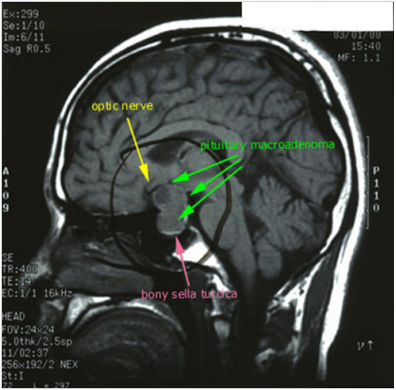

Tumor & Optic Nerve(literature’sreview)

Courtesy of Juliette Siegfried (www. brain-surgery. com).

A well-circumscribed mass is present within the expanded sellaturcica. This mass has suprasellar extension and demonstrates iso-intense signal on T1 weighted imaging, heterogeneous but predominantly low signal on T2 weighted imaging, and has predominantly peripheral enhancement, the lesion mildly bulges into the right cavernous sinus with no definite invasion. The optic chiasm is superiorly displaced by the mass and drapes over it. The lesion elevates anterior aspect of floor of the third ventricle without causing hydrocephalus.